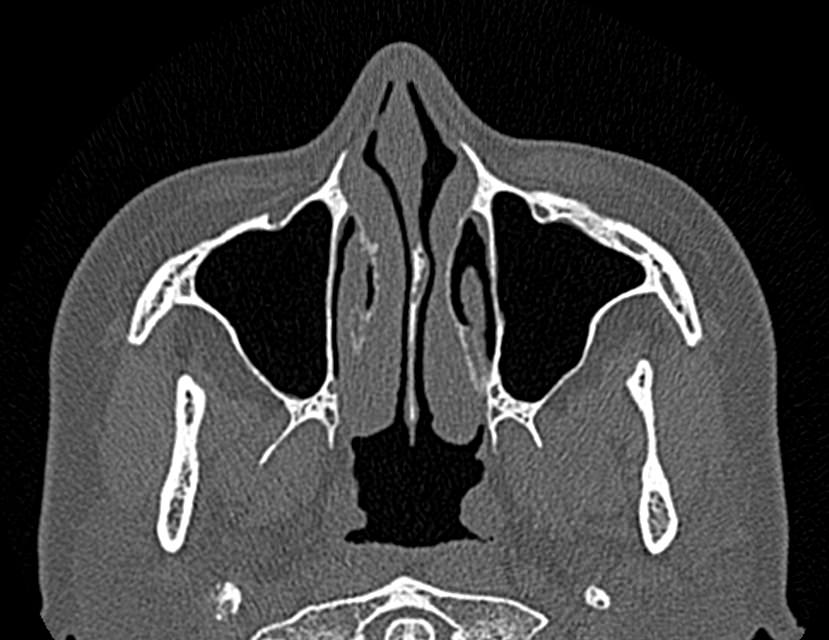

Золотым стандартом в диагностике патологических процессов пазух носа является мультиспиральная компьютерная томография, которая является быстрым безболезненным и неинвазивным (то есть без вмешательства в организм) способом исследования состояния синусов. Метод основан на проникающей способности ионизирующего излучения и получения изображений органов и тканей организма за счет разной степени поглощения ими рентгеновских лучей.

На основе полученных данных цифровые приложения томографов создают трехмерные реконструкции пазух носа, что позволяет оценить пространственное взаимоотношение анатомических структур и помогает в диагностике патологии околоносовых пазух.

Мультиспиральная компьютерная томография дает информацию о состоянии полости носа, носовой перегородки, степени воздушности околоносовых пазух, путей дренирования синусов, состоянии слезных каналов. Сканирование позволяет оценить толщину слизистой, наличие патологического содержимого в просвете пазух (уровня «жидкости»), выявить опухолевые образования. С помощью КТ можно провести точную диагностику травматических повреждений костей лицевого черепа, определить локализацию инородных тел, попавших в полости синусов.

С помощью объемной реконструкции можно перед оперативным вмешательством увидеть особенности анатомии ЛОР-органов, определить точное расположение патологического очага по отношению к окружающим тканям. Компьютерная томография помогает в диагностике аномалий развития придаточных пазух носа, слезоотводящих каналов.